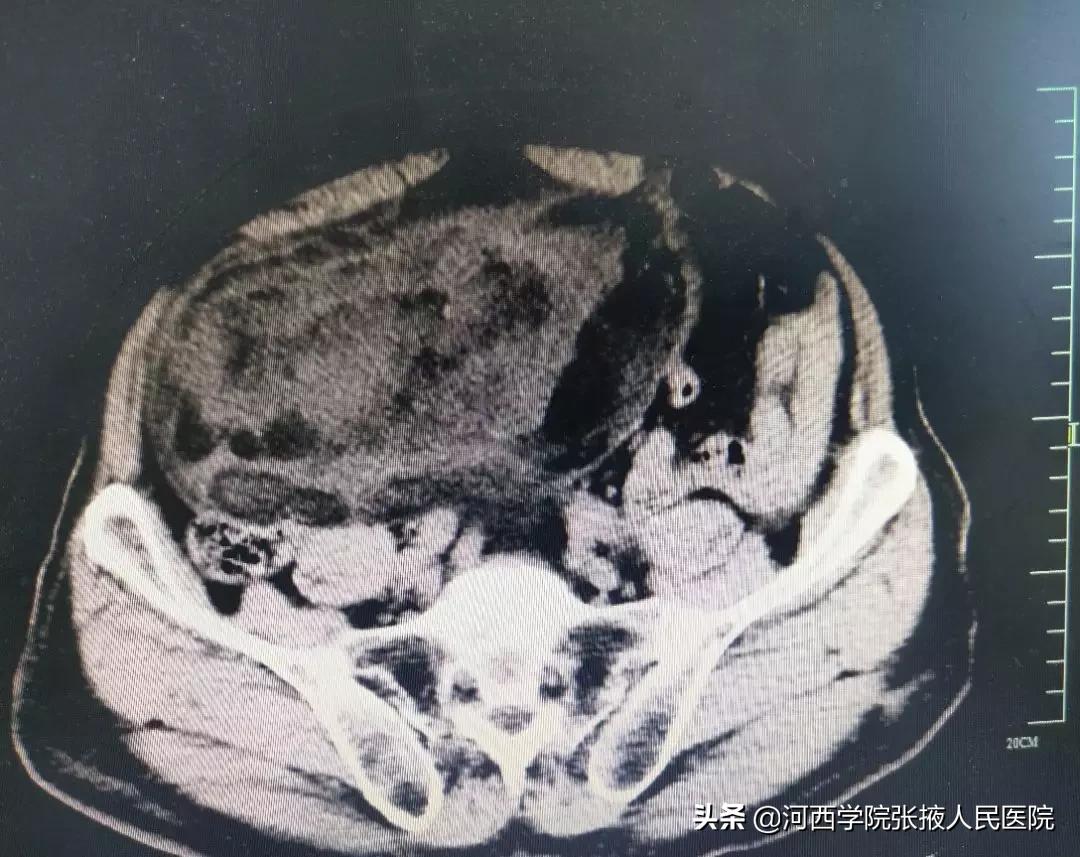

腹部CT检查示:右侧腹膜前间隙见巨大不规则混杂密度肿块影,病灶上缘起自十二指肠降部平面,下缘达膀胱上方,病灶边缘可见包膜,供血动脉来自右侧腹壁下动脉。提示:右侧腹膜前间隙巨大占位性病变,考虑脂肪肉瘤。

经反复阅片后积极术前准备,于2月25日,普外二科团队在全麻下为患者行腹膜后巨大肿瘤切除术,术中患者血压高至200/120mmHg,历经2个小时手术,79岁的张大爷在我院“甩”掉了腹内重达4公斤、直径约20cm的巨大肿瘤,那一刻生命重新起航。